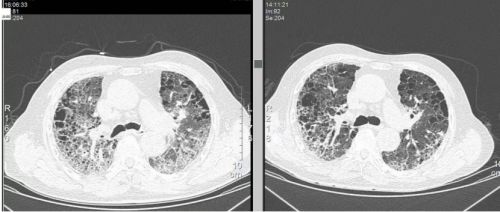

治疗后复查CT:

复查后氧合指数:272mmHg

治疗中早期联用该药物后,患者气道分泌物减少、氧合指数逐步改善,炎症指标(CRP、PCT)呈下降趋势,未出现明显不良反应,提示在重症肺部感染合并间质性肺病急性加重所致ARDS中,西维来司他钠可通过精准抗炎作用,辅助控制肺损伤进展,为抗感染、呼吸支持等综合治疗争取时间,其在多重感染诱发的重症肺损伤中的靶向治疗价值值得临床关注。